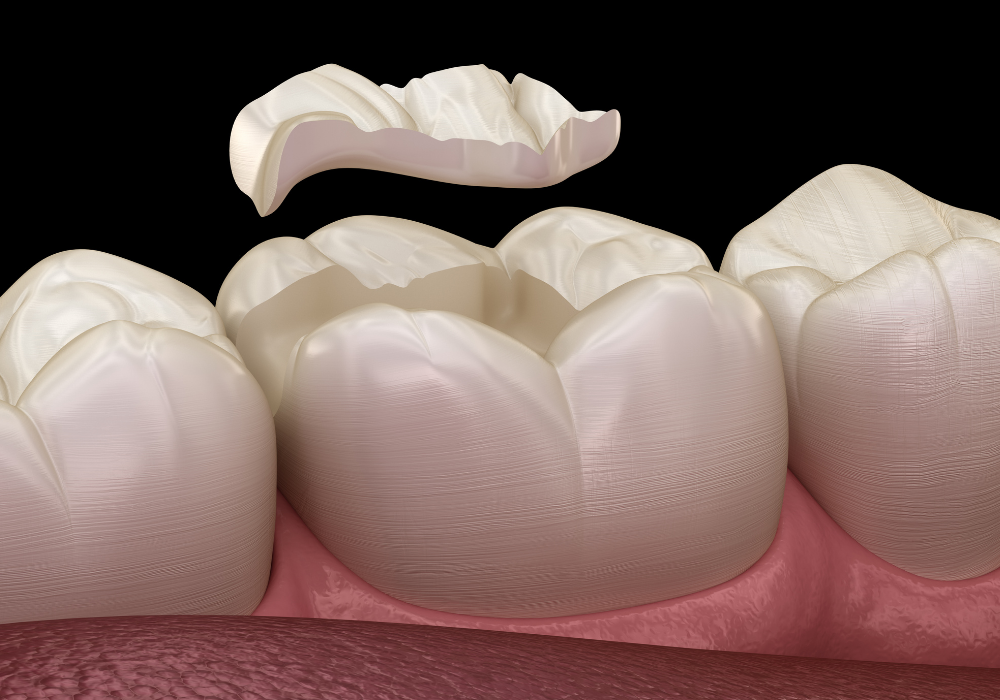

Estética dental (carillas y blanqueamiento)

Mejorá la apariencia de tu sonrisa con tratamientos que corrigen manchas, fracturas o asimetrías. Ofrecemos carillas estéticas y blanqueamientos que realzan tu imagen sin perder naturalidad.